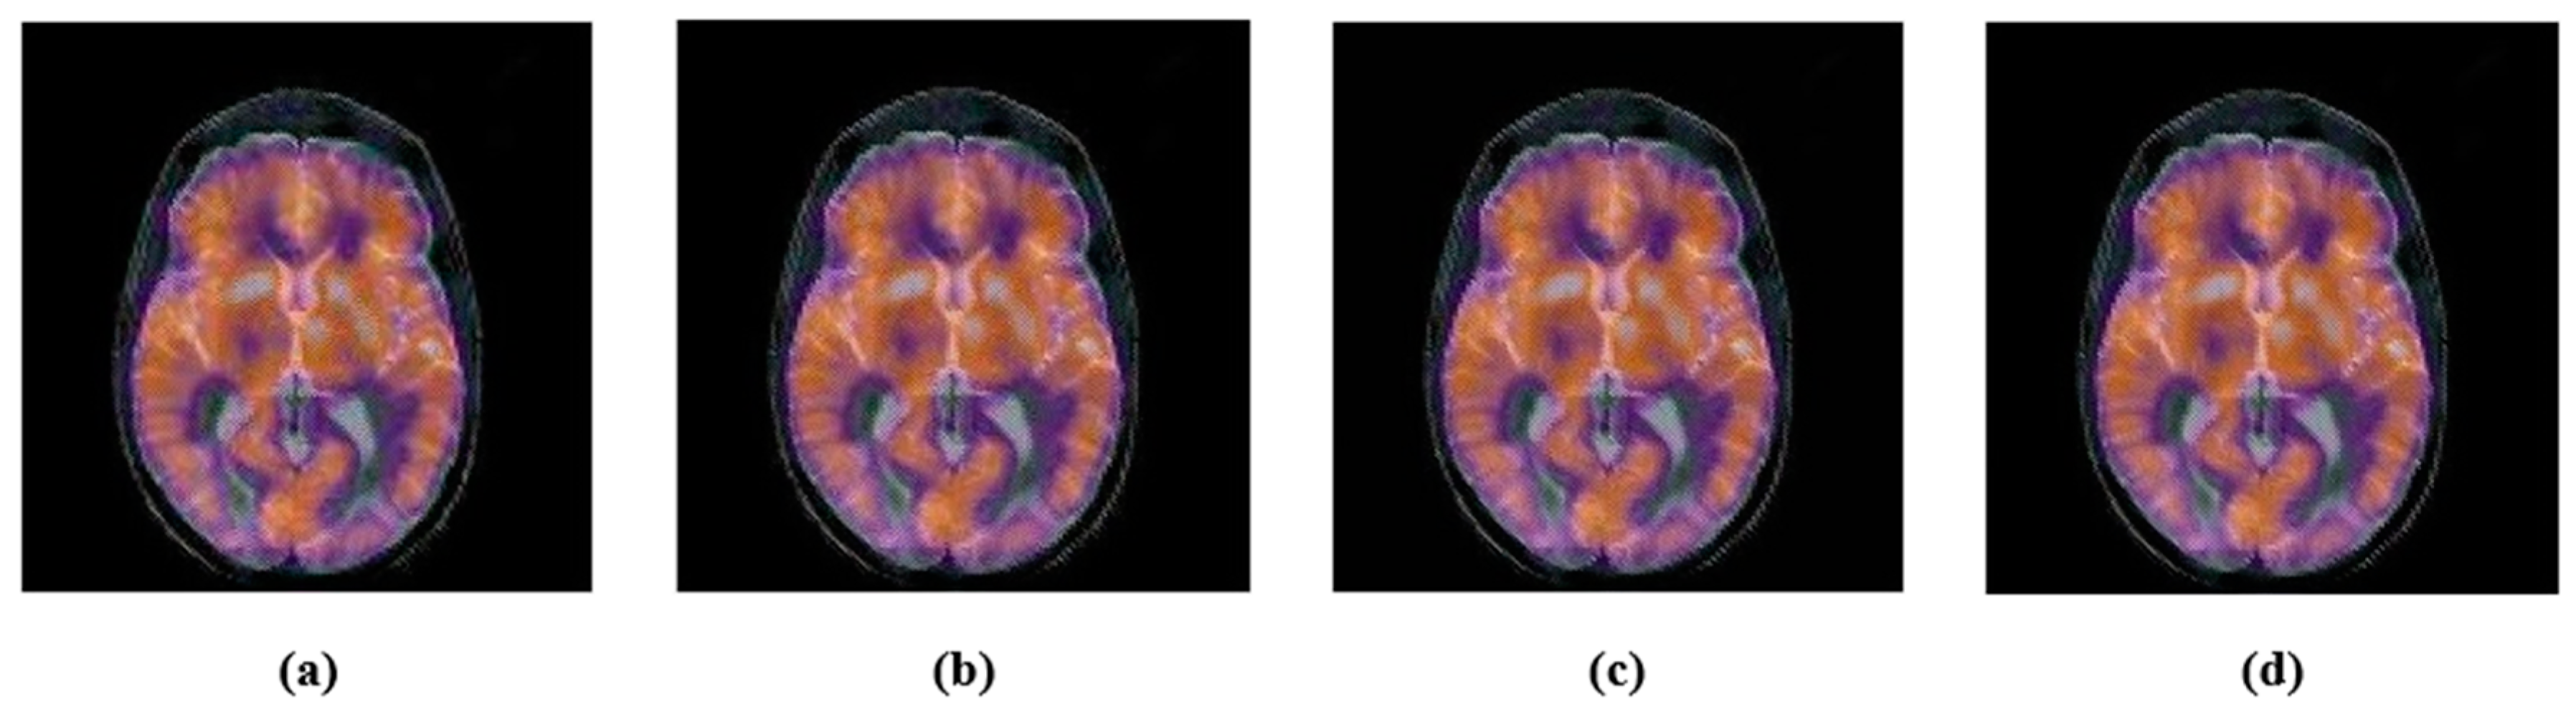

4.2. Robustness

4.2.1. Common Signal Processing Attacks